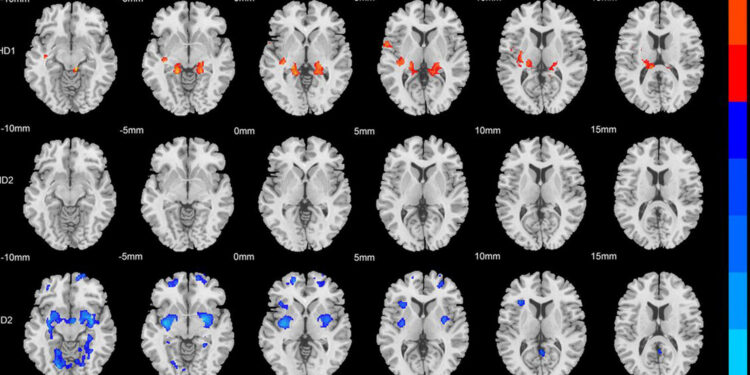

Read moreDetailsA recent brain imaging study reveals that attention deficit hyperactivity disorder consists of at least two distinct physical subtypes. This discovery suggests that patients may eventually benefit from highly personalized treatments based on their unique biology.